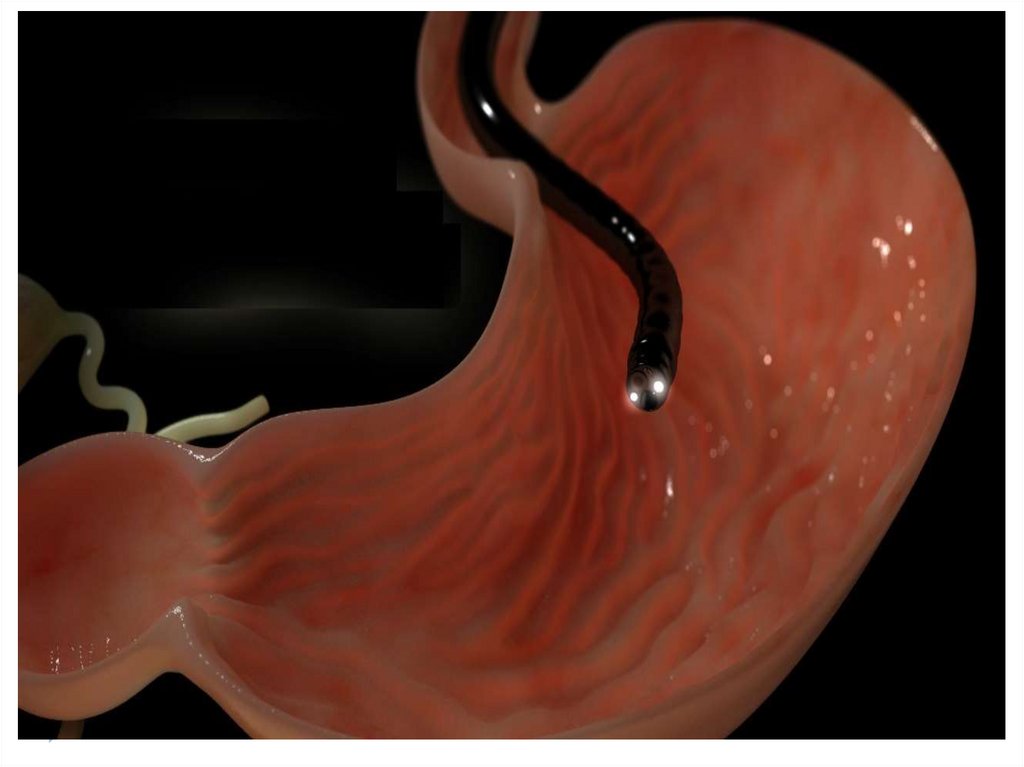

фиброэзофагогастродуоденоскопия (позволяет увидеть дефект

слизистой, определить его размеры и характер, взять кусочек

ткани для гистологического исследования);